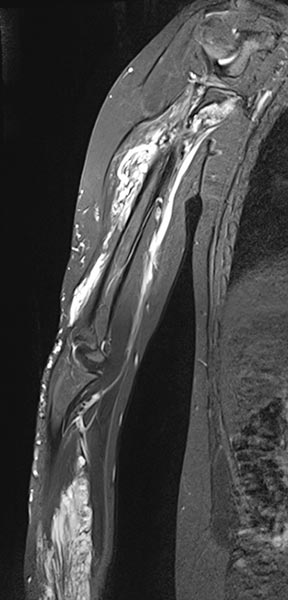

The coronal, T2-weighted, fat-suppressed sequence of an MRI with imaging of the right upper and lower arm shows a much larger extension of the malformation than clinically suspected.

The extension is predominantly subfascial in the depth of the muscles of the upper and lower arm. The signaling is strongly hyperintense, thus certainly a slow-flow malformation (venous or lymphatic).

The venous malformation shows deep extension in the deep flexor tendons of the hand and forearm on T2-weighted, fat-suppressed MRI.